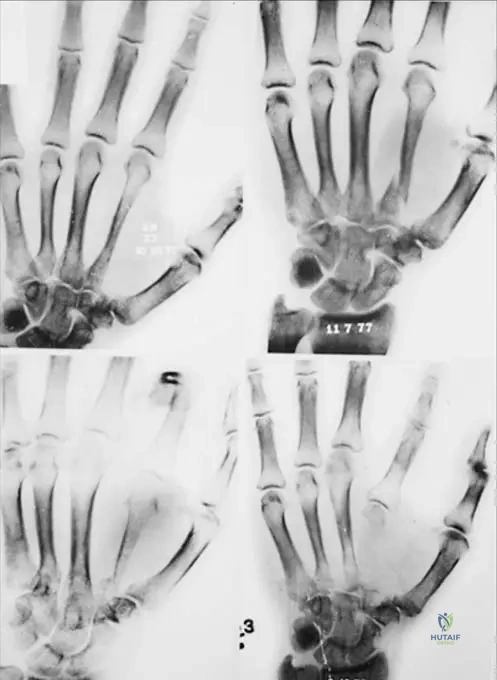

A 13-year-old male presents with an incidental finding of a nonossifying fibroma. The provided image, Fig. 11.16a, shows a characteristic location for these lesions. Which specific bone and region is depicted in Fig. 11.16a?

View Answer & Explanation

Correct Answer: C

Rationale: The image caption explicitly states, "Fig. 11.16 a–c These lesions are usually eccentric and metaphyseal, often occurring in the long bones of the lower extremity, including the distal femur (a) and distal (b) and proximal (c) tibia." Therefore, Fig. 11.16a depicts the distal femur.

A 16-year-old female is diagnosed with an asymptomatic nonossifying fibroma. The provided image, Fig. 11.16b, illustrates another common location for these lesions. Which specific bone and region is depicted in Fig. 11.16b?

Correct Answer: B

Rationale: The image caption explicitly states, "Fig. 11.16 a–c These lesions are usually eccentric and metaphyseal, often occurring in the long bones of the lower extremity, including the distal femur (a) and distal (b) and proximal (c) tibia." Therefore, Fig. 11.16b depicts the distal tibia.

A 10-year-old male presents with an incidental finding of a nonossifying fibroma. The provided image, Fig. 11.16c, demonstrates a third common location for these lesions. Which specific bone and region is depicted in Fig. 11.16c?

Rationale: The image caption explicitly states, "Fig. 11.16 a–c These lesions are usually eccentric and metaphyseal, often occurring in the long bones of the lower extremity, including the distal femur (a) and distal (b) and proximal (c) tibia." Therefore, Fig. 11.16c depicts the proximal tibia.